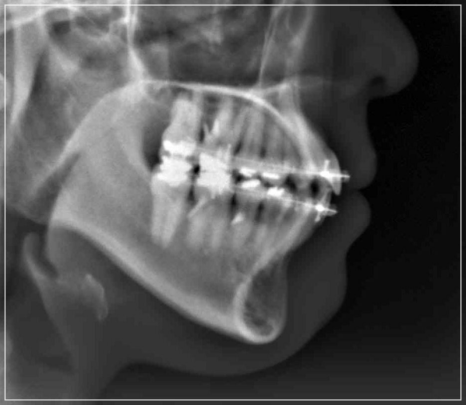

앞니가 안 다물어지는 상태를 개선한 모습

협조도가 저조하거나 근육의 적응력이

뒷받침되어 주지 않는다면 문제를

개선하는데 있어 분명한 한계점이

존재한다는 단점도 가지고 있습니다.

때문에 퇴행성 턱관절염으로 인해

개방교합이 발생한 경우에 해당된다면

위의 과정은 적합하지 않기에

다른 방법을 고려해보셔야 했는데요.

개방교합이 심해 장치 후 교정을 진행해야 하는 케이스입니다.

턱관절 급속 안정화 장치를 통해

퇴행성 관절염을 해결하여 더 이상

턱이 후퇴하여 개방교합이 생기지 않도록

안정화를 시킨 후 치아교정을 통해

입안다물어짐을 개선하고

없애주는 원리의 방식인데요.